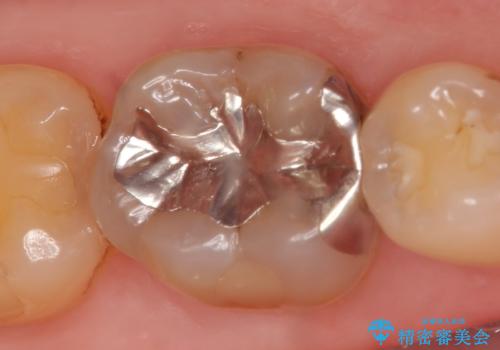

- 右下の銀歯を白くしたいといらっしゃった方の症例です。

銀歯を除去し、セラミックインレーによる修復を行いました。